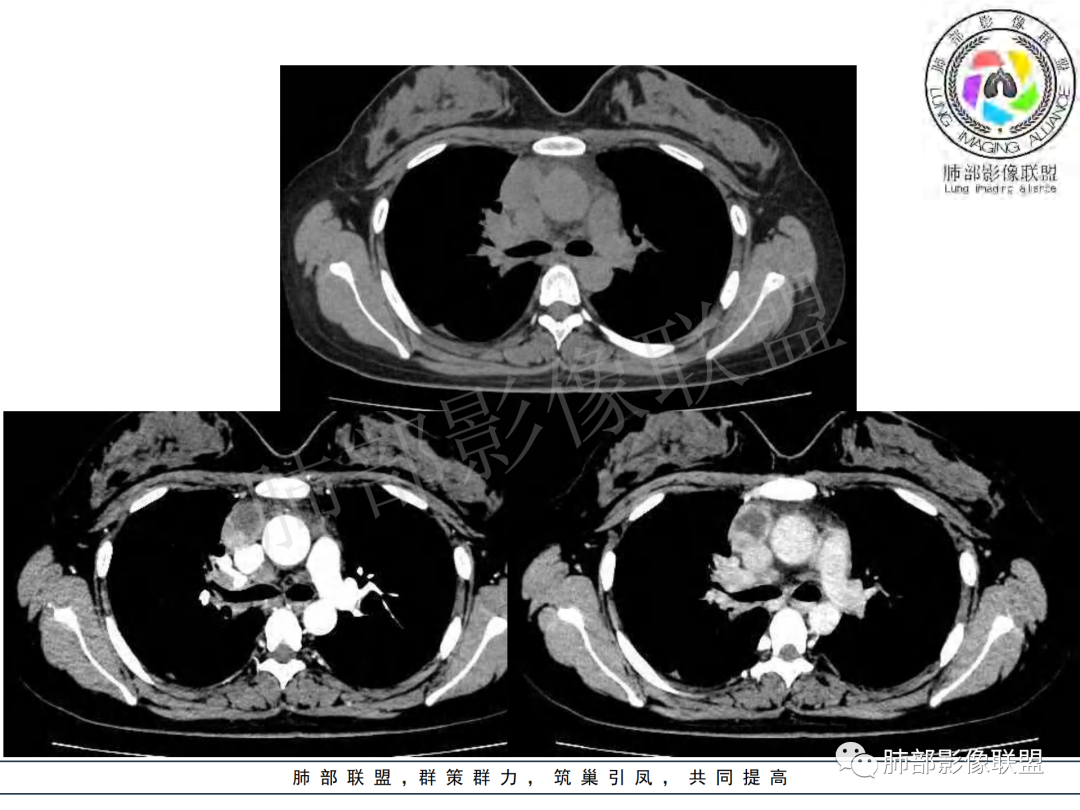

右肺肺门旁肿块,右肺中间段支气管腔内结节,增强强化不均;纵隔多发淋巴结环形强化,右侧少量胸腔积液,临床发热入院,考虑结核,鉴别肿瘤。

纵隔多组及右侧肺门多发肿大淋巴结,部分融合,不均匀强化,内见斑片状坏死区及环状强化,后者坏死边界尚清晰,肺门区肿大淋巴结与肺组织边界不清,年轻女性,8个月病史,发热首发症状,考虑淋巴结核并向肺内侵及(破溃?),鉴别淋巴瘤

女,20,病程长达8月,发热、胸痛、右侧胸腔积液病史。胸部CT:右肺门旁不规则肿块影,右中间支气管腔内结节,纵隔多发淋巴结肿大;强化不均匀,灶性坏死灶,环形强化;右侧少量胸腔积液并局部肉芽肿样突起。年轻女性,长病程,多部位,考虑慢性炎症,结核?鉴别肿瘤。

女性,20岁。高热、畏寒。右肺上叶近肺门区不规则肿块,周围斑点、片小结节影伴肿大淋巴结,肿块包绕并突入右主支气管腔内,增强后肿块不均匀强化,淋巴结环形强化中心低密度,考虑结核。

本例患者,年轻女性,慢性病程,多次抗感染治疗效果不佳,实验室检查示白细胞及中性粒细胞不高,不支持普通细菌感染,虽然肺泡灌洗液X-Pert检测阴性,结合患者胸部CT结核感染亦不能排除,胸部CT主要表现为右侧肺门及纵隔淋巴结肿大,仔细观察不难发现右中间支气管内新生物凸向管腔内,增强扫描,右肺门(10R)及纵隔淋巴结(2R,4R)明显不均匀强化,内部呈不规则低密度无强化区,被周边高强化区包绕(环形强化)的特点,首先应当想到纵隔淋巴结结核诊断。淋巴结分布亦不符合肺部恶性肿瘤迁徙途径。